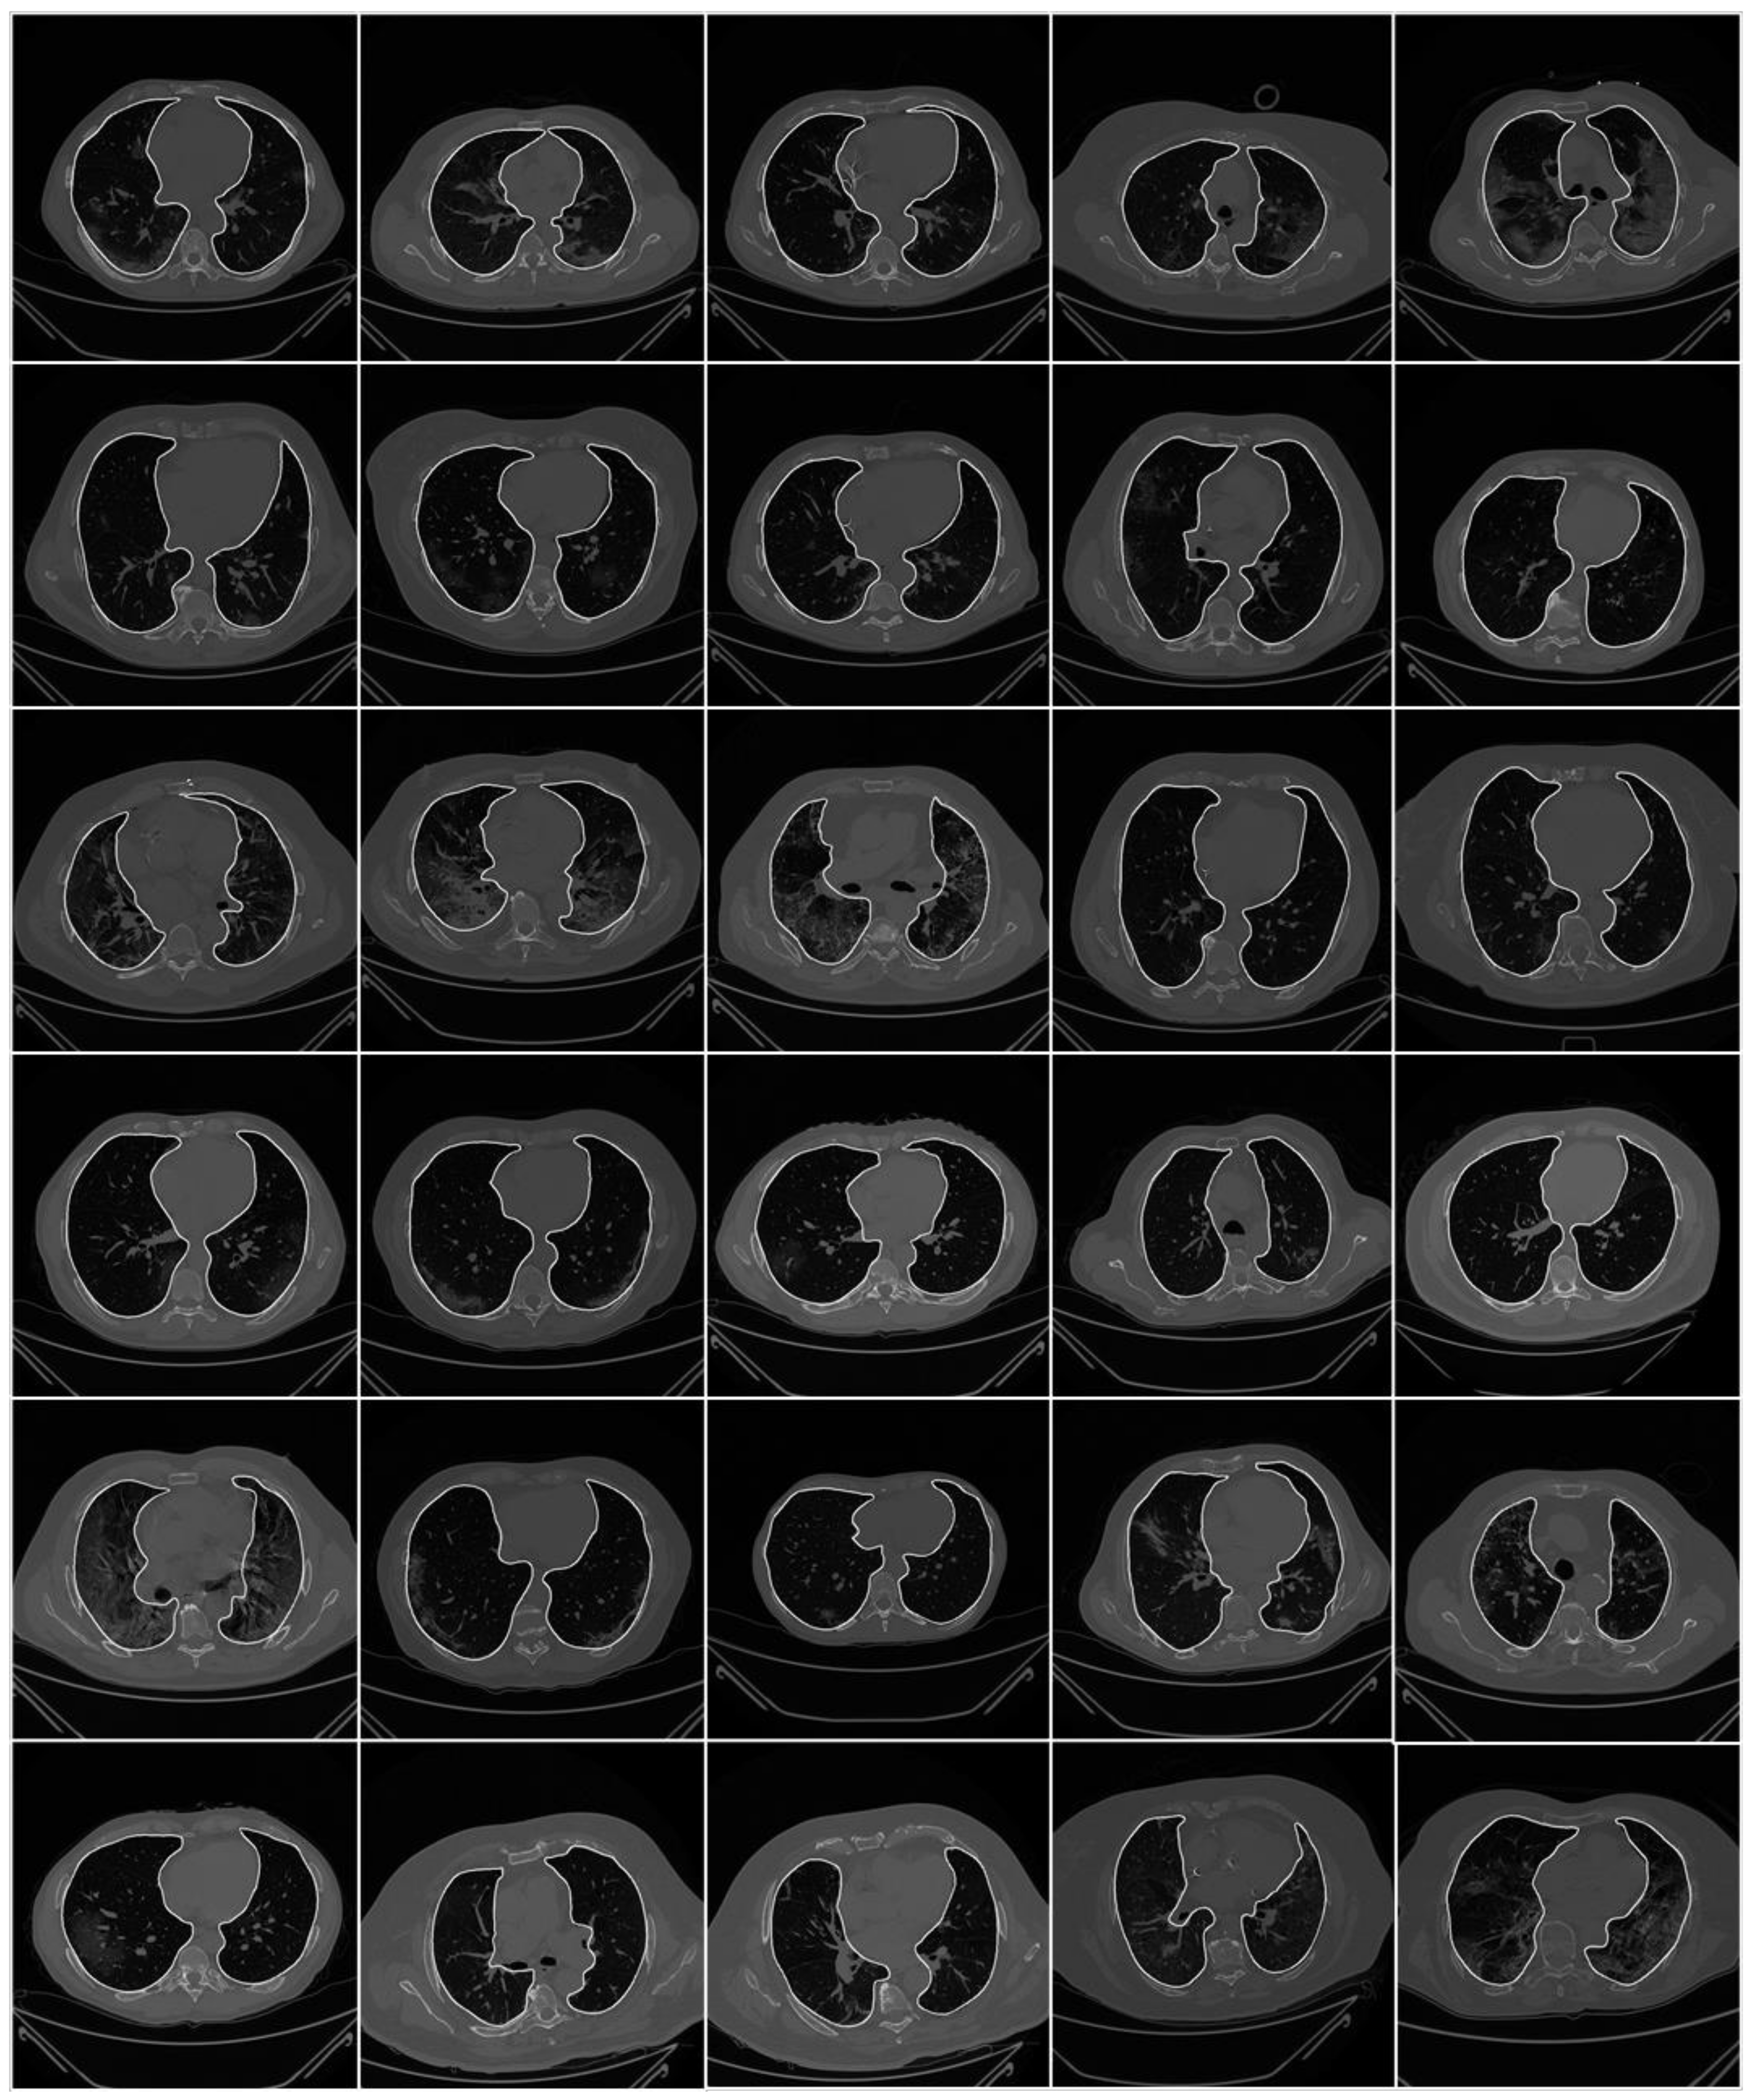

2.1. Patient Demographics, Image Acquisition, and Data Preparation

2.1.3. Data Preparation